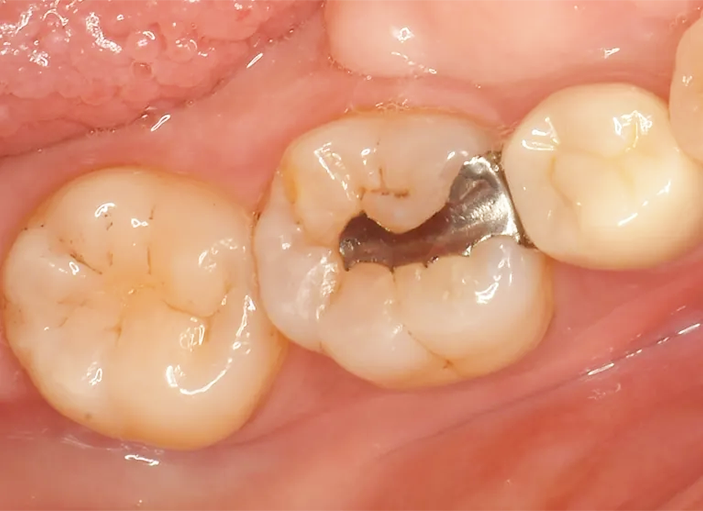

Case1

術前

ラバーダム防湿

術後

| 治療名 | ダイレクトボンディング |

|---|---|

| 治療説明 | 古い銀歯の下で虫歯が発生したため、ダイレクトボンディングを行いました。古い銀歯を除去し、ラバーダムを装着し、う蝕を除去してレジンを充填し、見た目と機能を回復しました。 |

| 治療回数・期間 | 1回 |

| 副作用とリスク | 知覚過敏症状が生じる恐れがあります。レジンが破折歯修復が必要となることがあります。 |

| 料金(税込) | 55,000円(自費) |